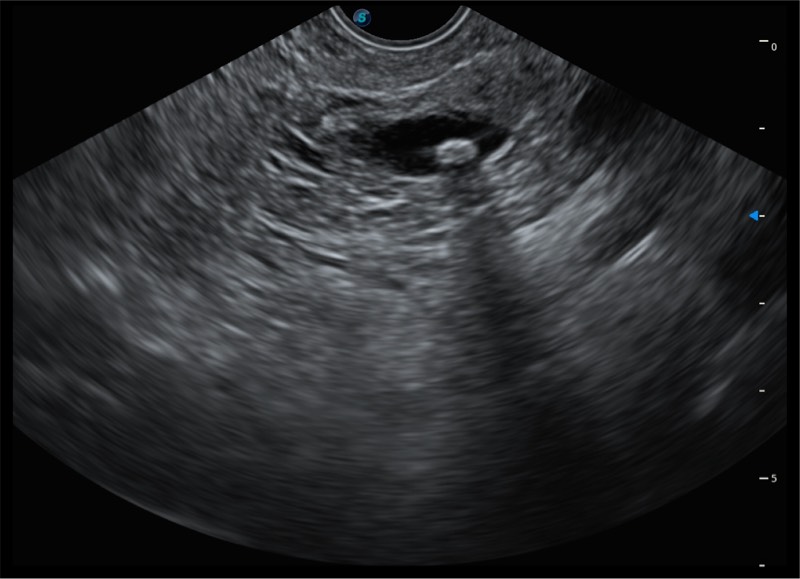

基于二十年的超声技术积累,MILE米乐集团官网提供了最新一代的独立超声主机,在提供高质量图像的同时满足多学科使用。具备常见多普勒技术并提供弹性成像、声学造影等高端影像技术。新一代传感器具有更强的抗干扰能力并减少图像伪影。